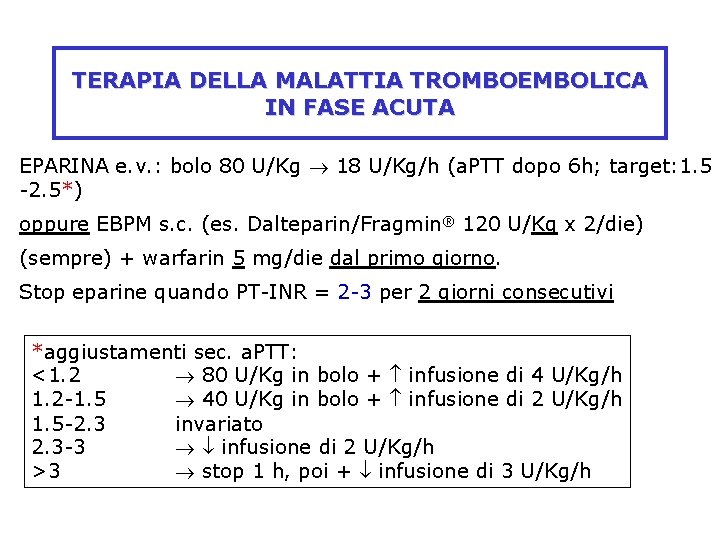

TERAPIA DELLA MALATTIA TROMBOEMBOLICA IN FASE ACUTA EPARINA e. v. : bolo 80 U/Kg 18 U/Kg/h (a. PTT dopo 6 h; target: 1. 5 -2. 5*) oppure EBPM s. c. (es. Dalteparin/Fragmin® 120 U/Kg x 2/die) (sempre) + warfarin 5 mg/die dal primo giorno. Stop eparine quando PT-INR = 2 -3 per 2 giorni consecutivi *aggiustamenti sec. a. PTT: <1. 2 80 U/Kg in bolo + infusione di 4 U/Kg/h 1. 2 -1. 5 40 U/Kg in bolo + infusione di 2 U/Kg/h 1. 5 -2. 3 invariato 2. 3 -3 infusione di 2 U/Kg/h >3 stop 1 h, poi + infusione di 3 U/Kg/h